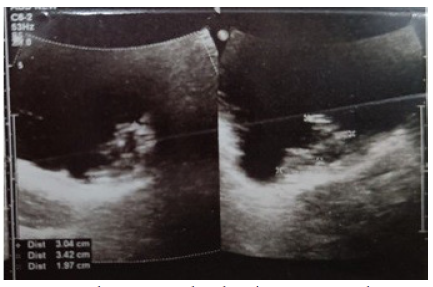

A 55-years-old female was admitted to our department with complaints of frequency, urgency, and nocturia. She had no significant medical history. Urinalysis revealed microscopic haematuria. Ultrasonography showed a 4 mm polyp in the urinary bladder near the left vesi­coureteric junction (VUJ) and increased bladder wall thickness (Figure 3).